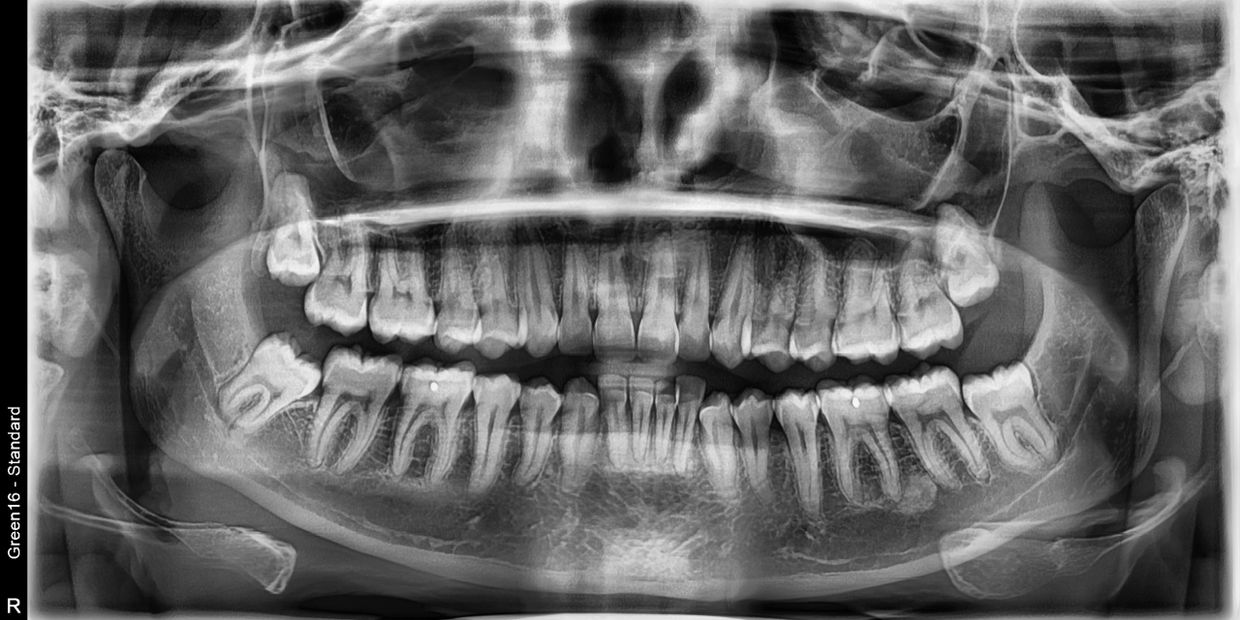

Tecnología avanzada—imágenes 3D y factores de crecimiento

El Dr. Martin es un cirujano oral y un especialista dental enfocado en tratar afecciones dentales y médicas complejas que involucran los dientes, la mandíbula, la boca y el rostro. Cuenta con amplia experiencia en procedimientos dentales como la extracción de muelas del juicio, implantes dentales y extracciones dentales. El Dr. Martin está dedicado a brindar la mejor experiencia posible a sus pacientes. Continúa su educación para garantizar que cada paciente reciba una atención óptima utilizando los avances más recientes en cirugía oral.